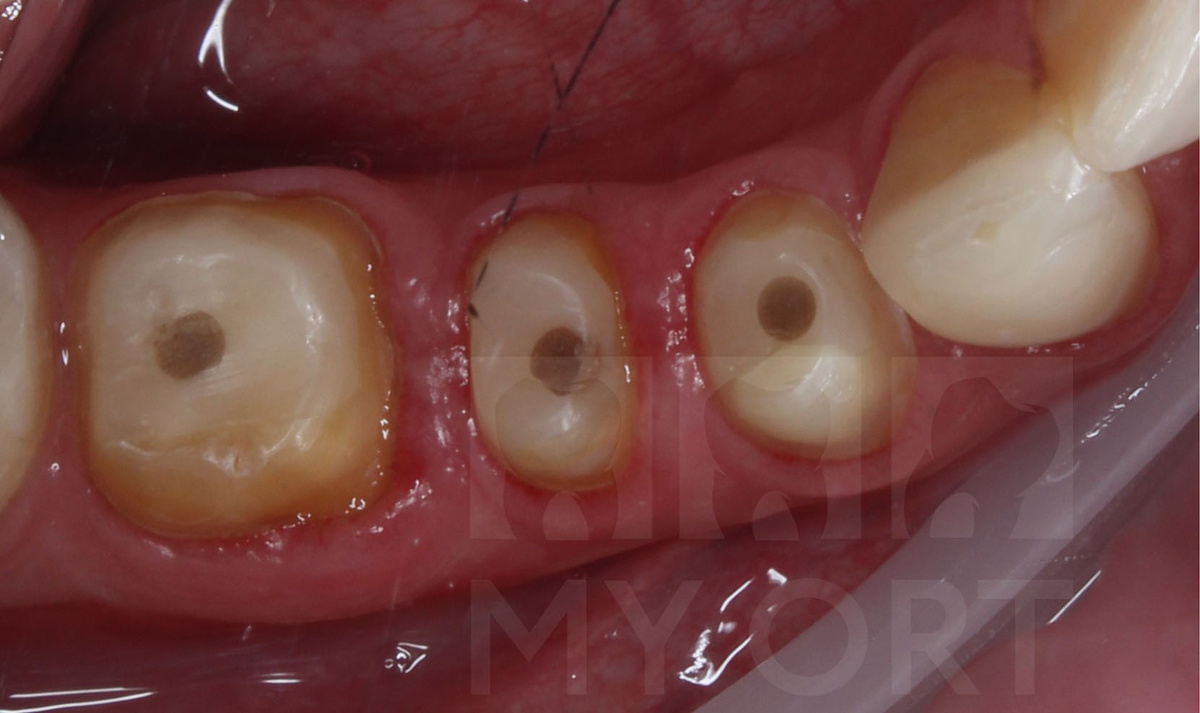

При осмотре пациента и проведения диагностики КТ я выявил, что у зубов отсутствует часть твердых тканей, стенки частично сколоты, а опора под дальнейшие реставрации была сильно ограничена.

Такие зубы находятся в зоне повышенного риска, ведь без полноценной защиты они не выдержат жевательную нагрузку и могут повторно разрушиться.

На первом этапе лечения я восстановил отсутствующие твердые ткани. В каждый зуб был установлен стекловолоконный штифт. Это позволило создать надежную опору и минимизировать риск перелома под жевательной нагрузкой.

Установлены стекловолоконные штифты